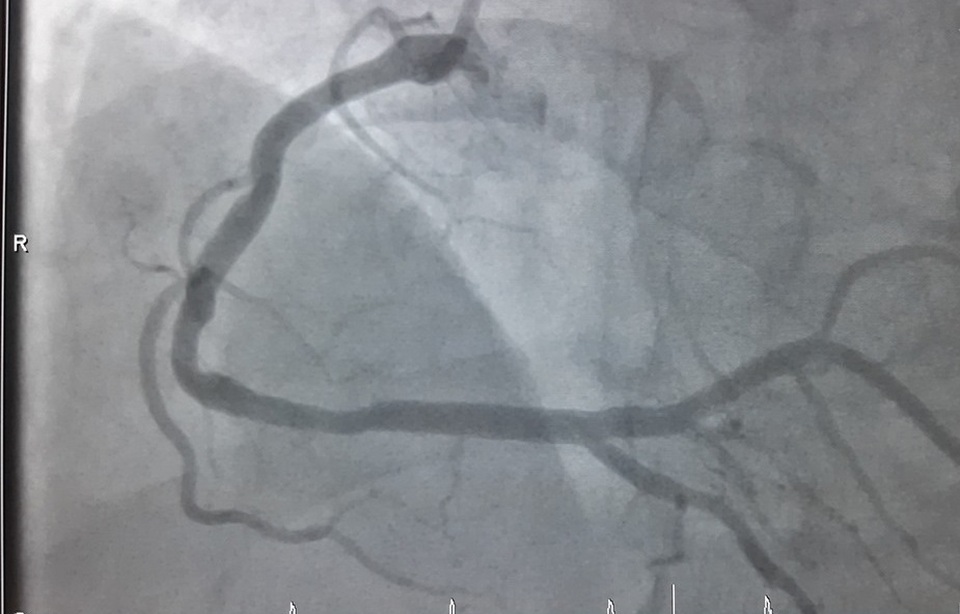

“Bệnh nhân vào viện vì đau ngực nhiều, nhịp tim chậm, huyết áp thấp. Chúng tôi tiến hành đo điện tâm đồ và phát hiện bệnh nhân bị nhồi máu cơ tim cấp nên đã hội chẩn khẩn và lập tức chuyển người bệnh vào phòng DSA chụp mạch vành cấp cứu”, bác sĩ Lạc nói.

Kết quả cho thấy, bệnh nhân bị tắc hoàn toàn động mạch vành bên phải. Các bác sĩ đã can thiệp nội mạch, đặt 1 stent tái lưu thông mạch máu cho bệnh nhân. Sau 30 phút khẩn trương, ê kíp đã đặt thành công sten tại vị trí bị tắc ở động mạch vành phải. Ngay sau khi can thiệp, bệnh nhân dần ổn định, hết đau ngực, nhịp tim huyết áp về bình thường.